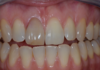

Aspect esthétique à 15 jours

Excellente maturation gingivale...